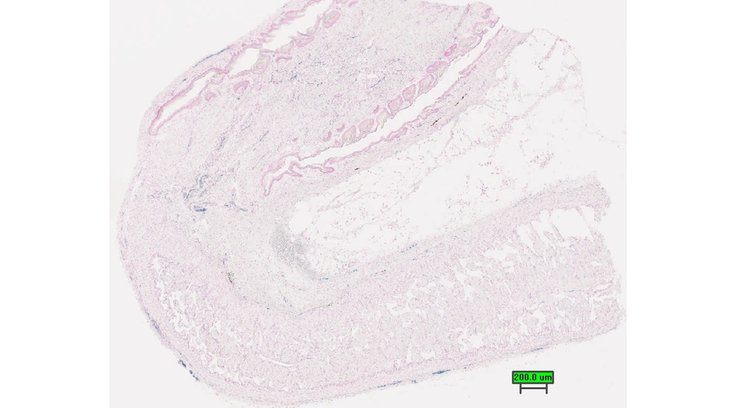

TS28: penis Present UC Davis_1878935

TS28: penis Present UC Davis_1878936

TS28: penis Present UC Davis_1878937